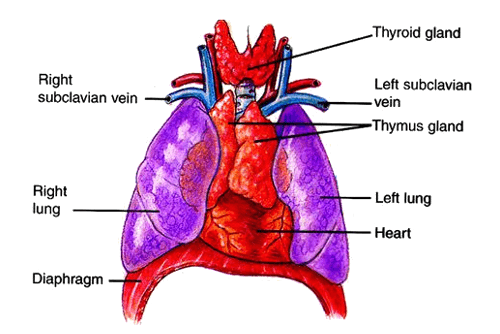

Фотографии вилочковой железы тимуса: структура и функции